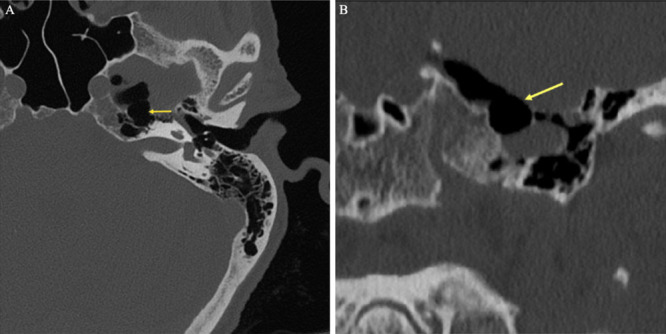

Background: Spontaneous pneumocephalus is a rare, but potentially serious condition often secondary to a CSF leak. This egress of CSF causes an inward movement of air to replace the lost volume. CSF leaks are typically posttraumatic and present as rhinorrhea or otorrhea. Locating the bony defect and herniating contents through imaging is crucial for planned surgical intervention. In this report, the author present the case of a patient with progressive spontaneous pneumocephalus with an apparent but unidentifiable CSF leak.

Observations: A 76-year-old female presented to the authors' institution with rapidly progressing spontaneous pneumocephalus. This case is unique in that the patient's pneumocephalus continued to expand without any radiological indication of extracranial CSF, leading us to believe that the CSF was intermittently leaking through the eustachian tube and passing down the patient's oropharynx. Given the presumed pathway, an initial conservative surgical approach was chosen for this patient's spontaneous pneumocephalus instead of the traditional middle cranial fossa or transmastoid approach.